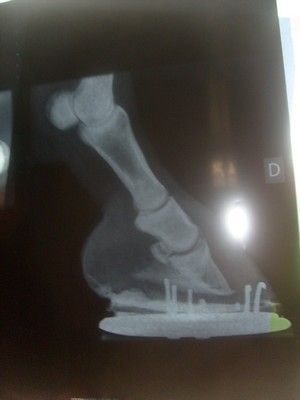

Par guigui6 : le 15/12/10 à 20:32:03

| Dire merci | ça c'est prévu les radios on va dire que j'attendais le cap des 1 an Le truc c'est que je n'ai pas fait de radios une fois déférée mais quand elle avait encore ses fers a l'envers et ça donné ça, photos des radios, sur mon scanner ça ne marche pas. ![]() ![]() on verra ce que ça donnera |